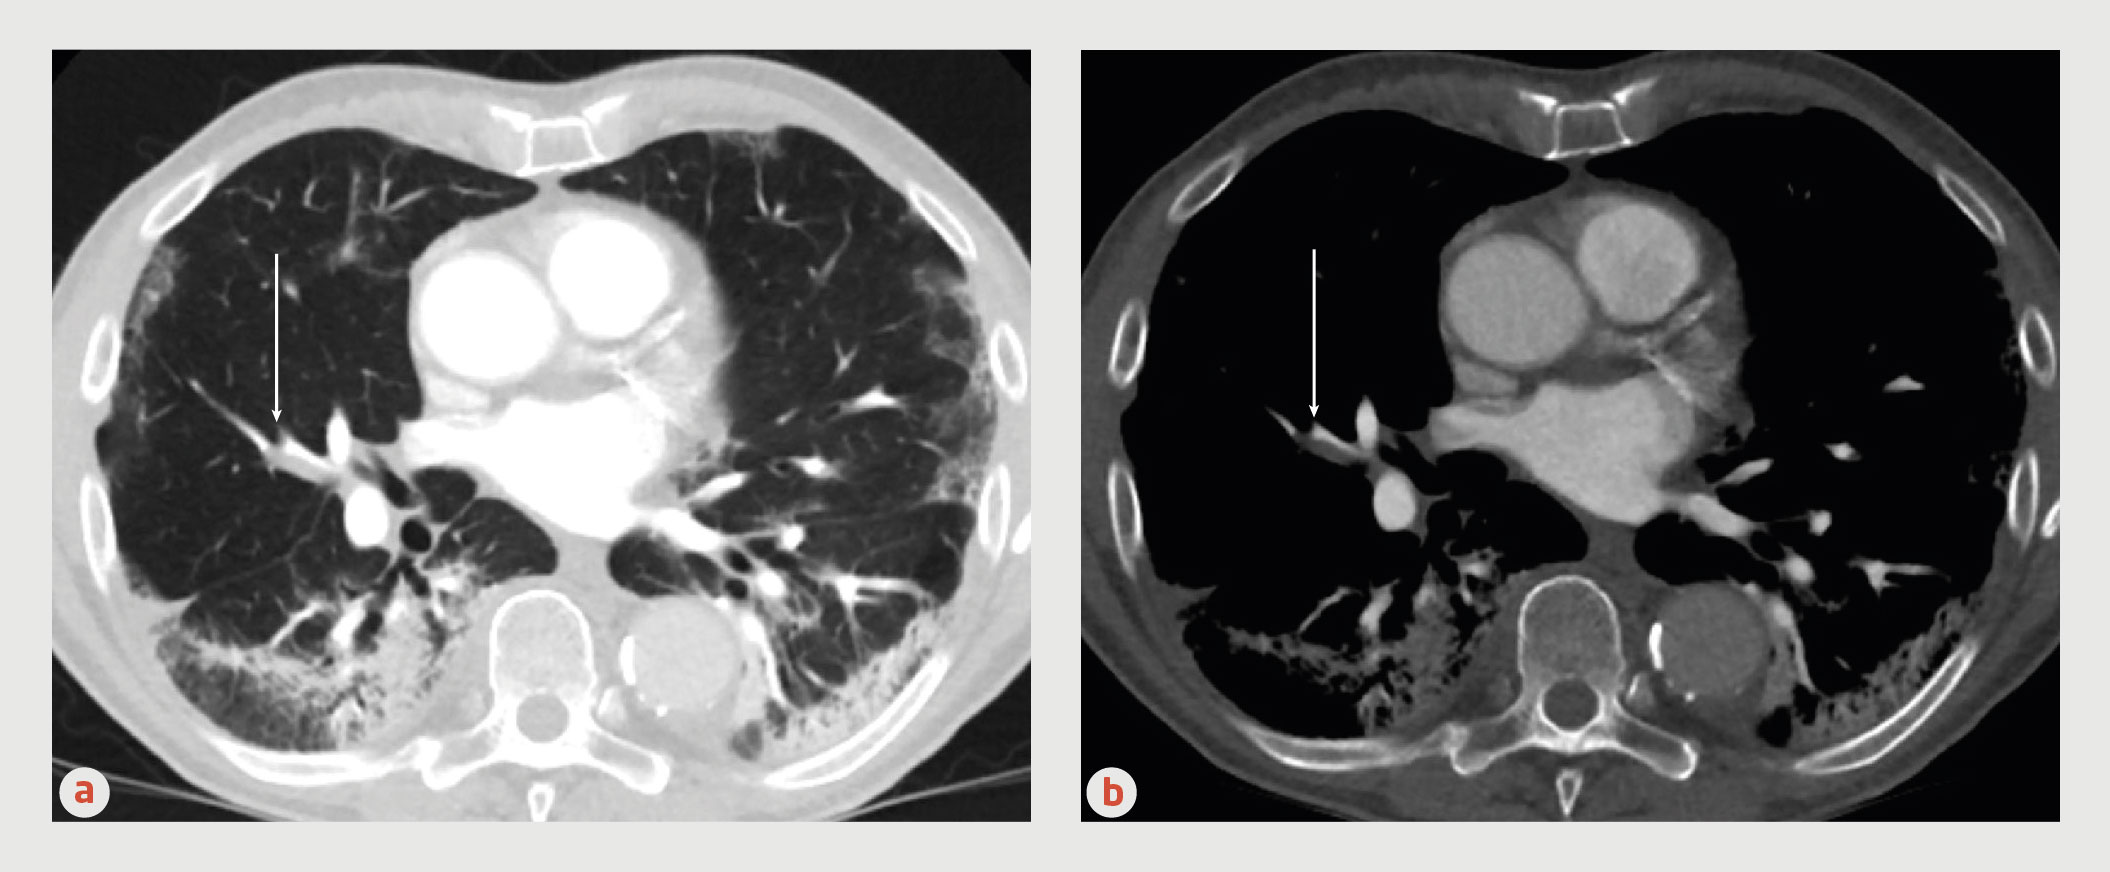

Een 80-jarige vrouw met kortademigheid door myxoma cordis ...

Een 80-jarige vrouw met kortademigheid door myxoma cordis ... from www.ntvg.nl